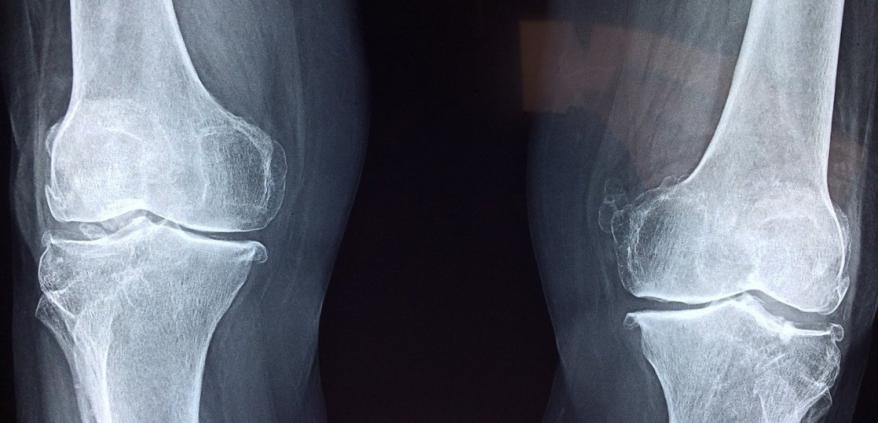

类风湿性关节炎的关节破坏是进行性的,被破坏的话是不可逆的。也就是说,即使进行治疗,也很难恢复到原来的关节状态。因此,期待使用干细胞的治疗是关节功能的再生和其必要的细胞的再生。这个再生医疗中使用的细胞,被期待着是iPS细胞和间叶系干细胞。

临床案例2:据《Stem Cells》期刊报道,在一项 I/II 期临床试验中,研究人员对患者进行膝关节内注射间充质干细胞,干细胞发挥修复透明软骨的作用,减少了MRI确定的软骨缺损,并且改善了患者膝关节的功能和疼痛,无并发症发生。